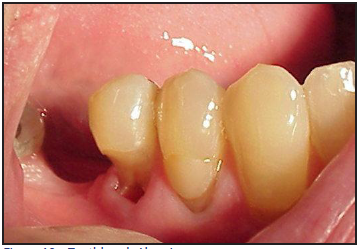

Tooth and gingival abrasion are defined as pathologic wear as a result of a foreign substance (Figure 10). Abrasion is multi-factorial but is generally believed to be caused by over-zealous toothbrushing. Studies have also reported an increase in cervical lesions in people who brush with greater frequency, for longer periods of time and use the "scrubbing" brushing technique.34,35

Gingival abrasion - trauma to the gingival tissue which frequently occurs on the facial surfaces.

Figure 10 – Toothbrush Abrasion

Figure 10